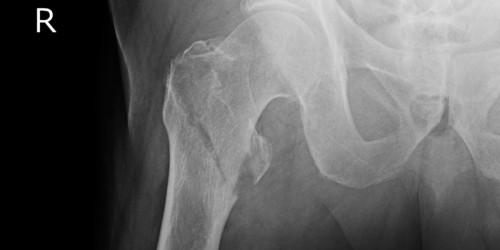

I have a haematoma in hip for 4 months and a numbness to leg and foot a m.r.i scan has revealed that it is pinching on a nerve and I am getting fed up with doctors saying it will take time may be another 6 months icant even walk and in constant pain and I would be so glad to hear if anyone has had it removed and how long did it take to recover also was it sore to get it done